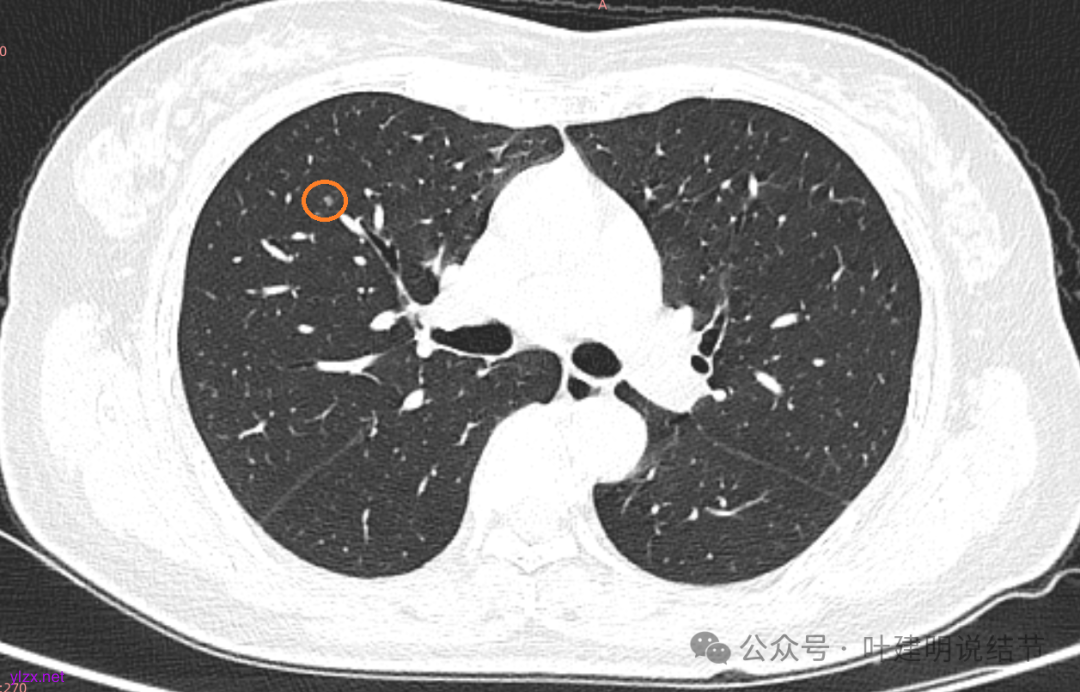

先来看2025年3月的影像:

两肺多发磨玻璃结节,我们主要看最主要的病灶有没有风险或者有没有进展就可以。我是先看2025年的,黄色的微小磨玻璃结节,密度很低,但是轮廓较为清楚,需要考虑肺泡上皮增生或者肺泡间隔增宽,严格意义上应该没有算肺癌,但是以后有可能会发展到不典型增生或者原位癌,当然也可能永远发展不到那个程度,所以目前不需要管;蓝色的到底是肺泡上皮增生还是少许慢性炎不太好确定,因为轮廓稍显模糊,但它又是磨玻璃密度,总归近期是能够随访的;橘色的密度比黄色的略高,有可能会使肺泡上皮增生或者不典型增生,目前也仍可以随访;粉色的是主病灶,位于左肺上叶,混合密度,表面毛糙,由小血管进入,单次看需要考虑微浸润性腺癌可能性较大。然后我们再来看2020年的影像,因为除了粉色的其他的都没有风险,所以不需要一一去找出来,重点关注粉色这处当时是怎样的。我们发现这个病灶5年前就有,也有小血管进入,也有表面毛糙,也是磨玻璃密度,但是当时磨玻璃当中没有实性的成分,是纯磨玻璃伴微小血管进入。对比起来看,这个病灶在5年当中略有进展,原来应该是腺体前驱病变,现在应该是原位癌或者微浸润性腺癌。那么是不是现在就到了一定得马上手术的程度呢?这个仍然可能是不同医生意见会有出入的。假如说从再随访是不是马上会转移来讲,这么小的肿瘤,发展这么慢,而且仍然含有磨玻璃成分,病理考虑与微浸润性腺癌可能性较大,应该仍然不至于说没有随访的空间。但是如果继续随反思想压力比较大,以及即便在随访后续仍然总得要开刀来说,加上病灶位置靠胸膜并不远,简单的单孔胸腔镜楔形切除就能解决问题,将有一定风险的这个病灶切了,同样是可行的。这需要你自己权衡决定。我没有办法100%给十分确切的意见。但是如果从倾向性来讲,由于是多发病灶,加上年纪还轻,风险还不是很大,稍微清一下雨6~9个月复查,有进展病风险再增加再考虑手术。意见供你参考!